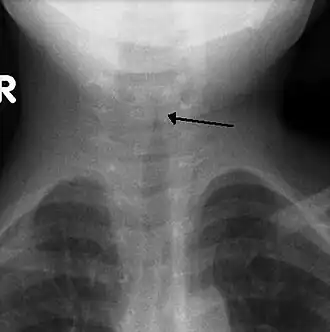

Pseudokroep (laryngitis subglottica of valse kroep) is een virale ontsteking van de bovenste luchtwegen, in de buurt van de stembanden. Meestal wordt deze infectie door een verkoudheid voorafgegaan.

Door de ontsteking zwellen de slijmvliezen rondom de stembanden op. Daardoor wordt het inademen moeilijker en kan benauwdheid optreden. Het ademen gaat vaak gepaard met een gierend geluid (= inspiratoire stridor). Het stemgeluid is meestal hees. Ook kan een stevige blafhoest voorkomen. De lichaamstemperatuur is normaal, of hooguit 38 graden.